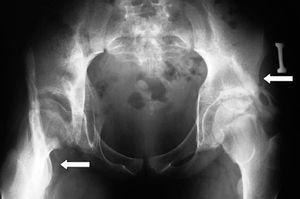

Caso 2. Niña diagnosticada de FOP a los 3 años por limitación para la flexión de rodilla derecha y calcificaciones en tejidos blandos, hallux valgus y clinodactilia. Los antecedentes familiares carecían de interés. Nos fue remitida desde el servicio de Ortopedia en 1994, a los 13 años, por dolor mecánico en ingle derecha. La exploración mostró contractura en extensión y ausencia de movilidad del codo y la rodilla derechos, flexo de 40° no reducible en la cadera derecha, e imposibilidad para las rotaciones, aunque flexionaba hasta 90º en la cadera izquierda. La capacidad para deambular estaba muy limitada. La radiografía de caderas demostró calcificaciones de tejidos blandos (fig. 3). Desde los 15 años se objetivó trastorno ventilatorio restrictivo moderado. El cuadro progresó a pesar de tratamiento con alendronato 10 mg diarios y de la administración de indometacina y corticoides en los episodios de dolor y tumefacción. A los 20 años fue perdida para el seguimiento.

Figura 3. Calcificaciones en partes blandas.